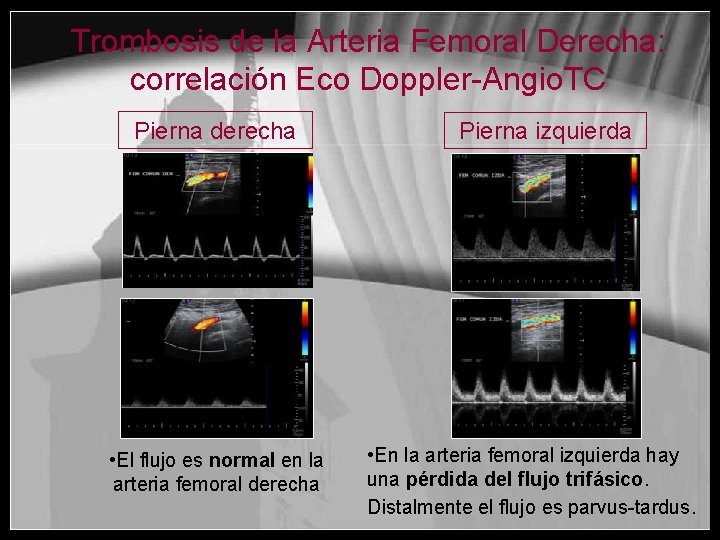

Trombosis de la Arteria Femoral Derecha: correlación Eco Doppler-Angio. TC Pierna derecha • El flujo es normal en la arteria femoral derecha Pierna izquierda • En la arteria femoral izquierda hay una pérdida del flujo trifásico. Distalmente el flujo es parvus-tardus.